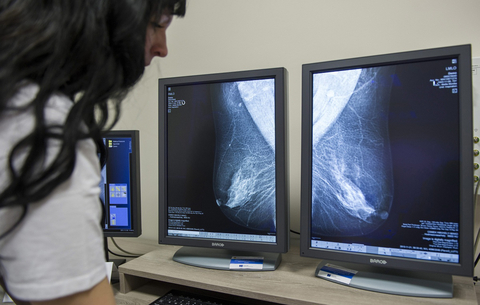

Egy nemzetközi kutatócsoport átfogó képet festett a melldaganatok trendjei és egy adott ország fejlettségének kapcsolatáról. Adataik óriási szakadékot mutatnak a túlélési arányokban, attól függően, ki, hol él.